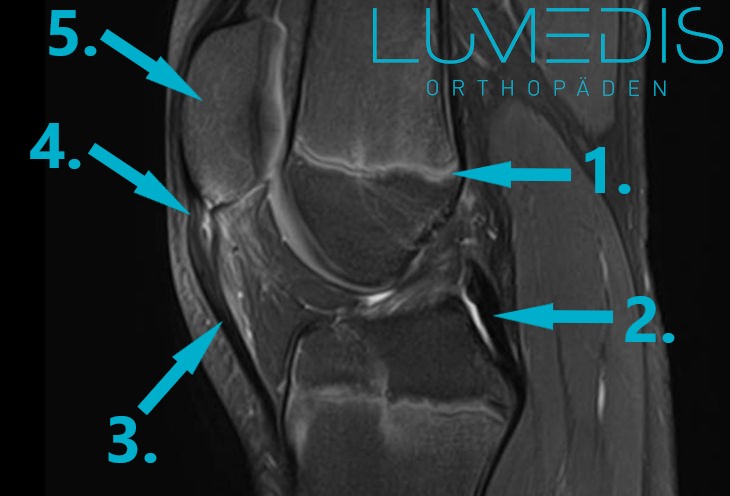

MRT eine teilgerissenen (obere Bild) und gesunden Patellarsehne (untere Bild)

Eine MRT-Untersuchung des Knies kommt immer dann zur Anwendung, wenn man eine Verletzung von Sehnen, Muskeln oder Menisken und Bändern beweisen will. Auch bei einem Verdacht einer Patellasehnenverletzung und unauffällig vorangegangenen Untersuchungen kann die Durchführung einer MRT-Untersuchung sinnvoll sein. In der strahlungsfreien Schnittbilduntersuchung sieht man alle Gewebe des Knies. Einen Anriss oder Durchriss der Patellasehnekönnte man somit auch eindeutig beweisen.